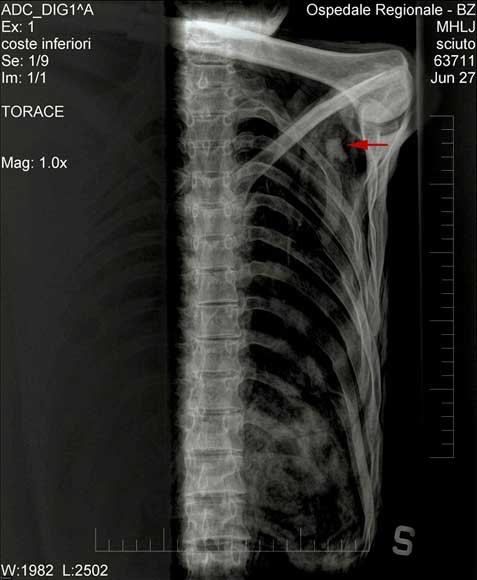

Quá trình kiểm định xác ướp hơn 5300 năm tuổi